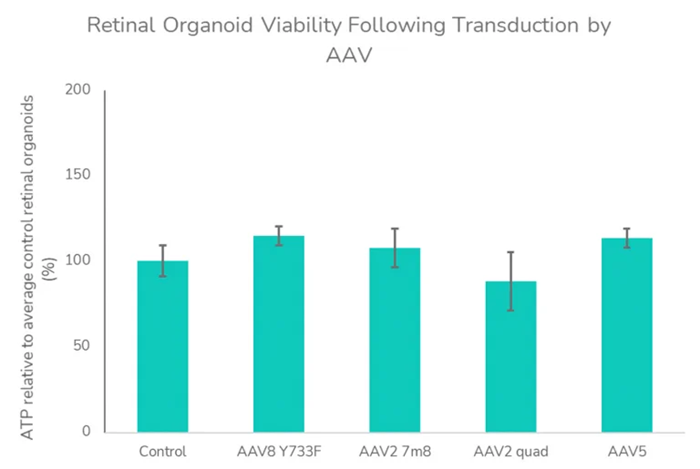

The experiments demonstrated that a CAG-driven transgene transduced various cell types, whereas GRK1-driven transgenes exhibit a more limited photoreceptor-specific expression (A). This was because the organoids contained multiple cell types, which allowed the experiments to display the targeted cell types specifically. The study also showed that AAV transduction did not affect the retinal organoids’ viability (B).

(B) Retinal organoid viability following transduction by AAV. ATP assay was assessed as an indicator of viability at 27 days post-transduction with AAV vectors. Data analyzed using a one-way analysis of variance indicated no significant influence of AAV treatment on ATP levels and viability (F=1.107, P =0.3908) relative to control retinal organoids. Image To enable quick assessment of novel retinal gene therapy vectors, these investigations can be conducted in both retinal organoids and RPE in vitro models. Image Credit: Newcells Biotech